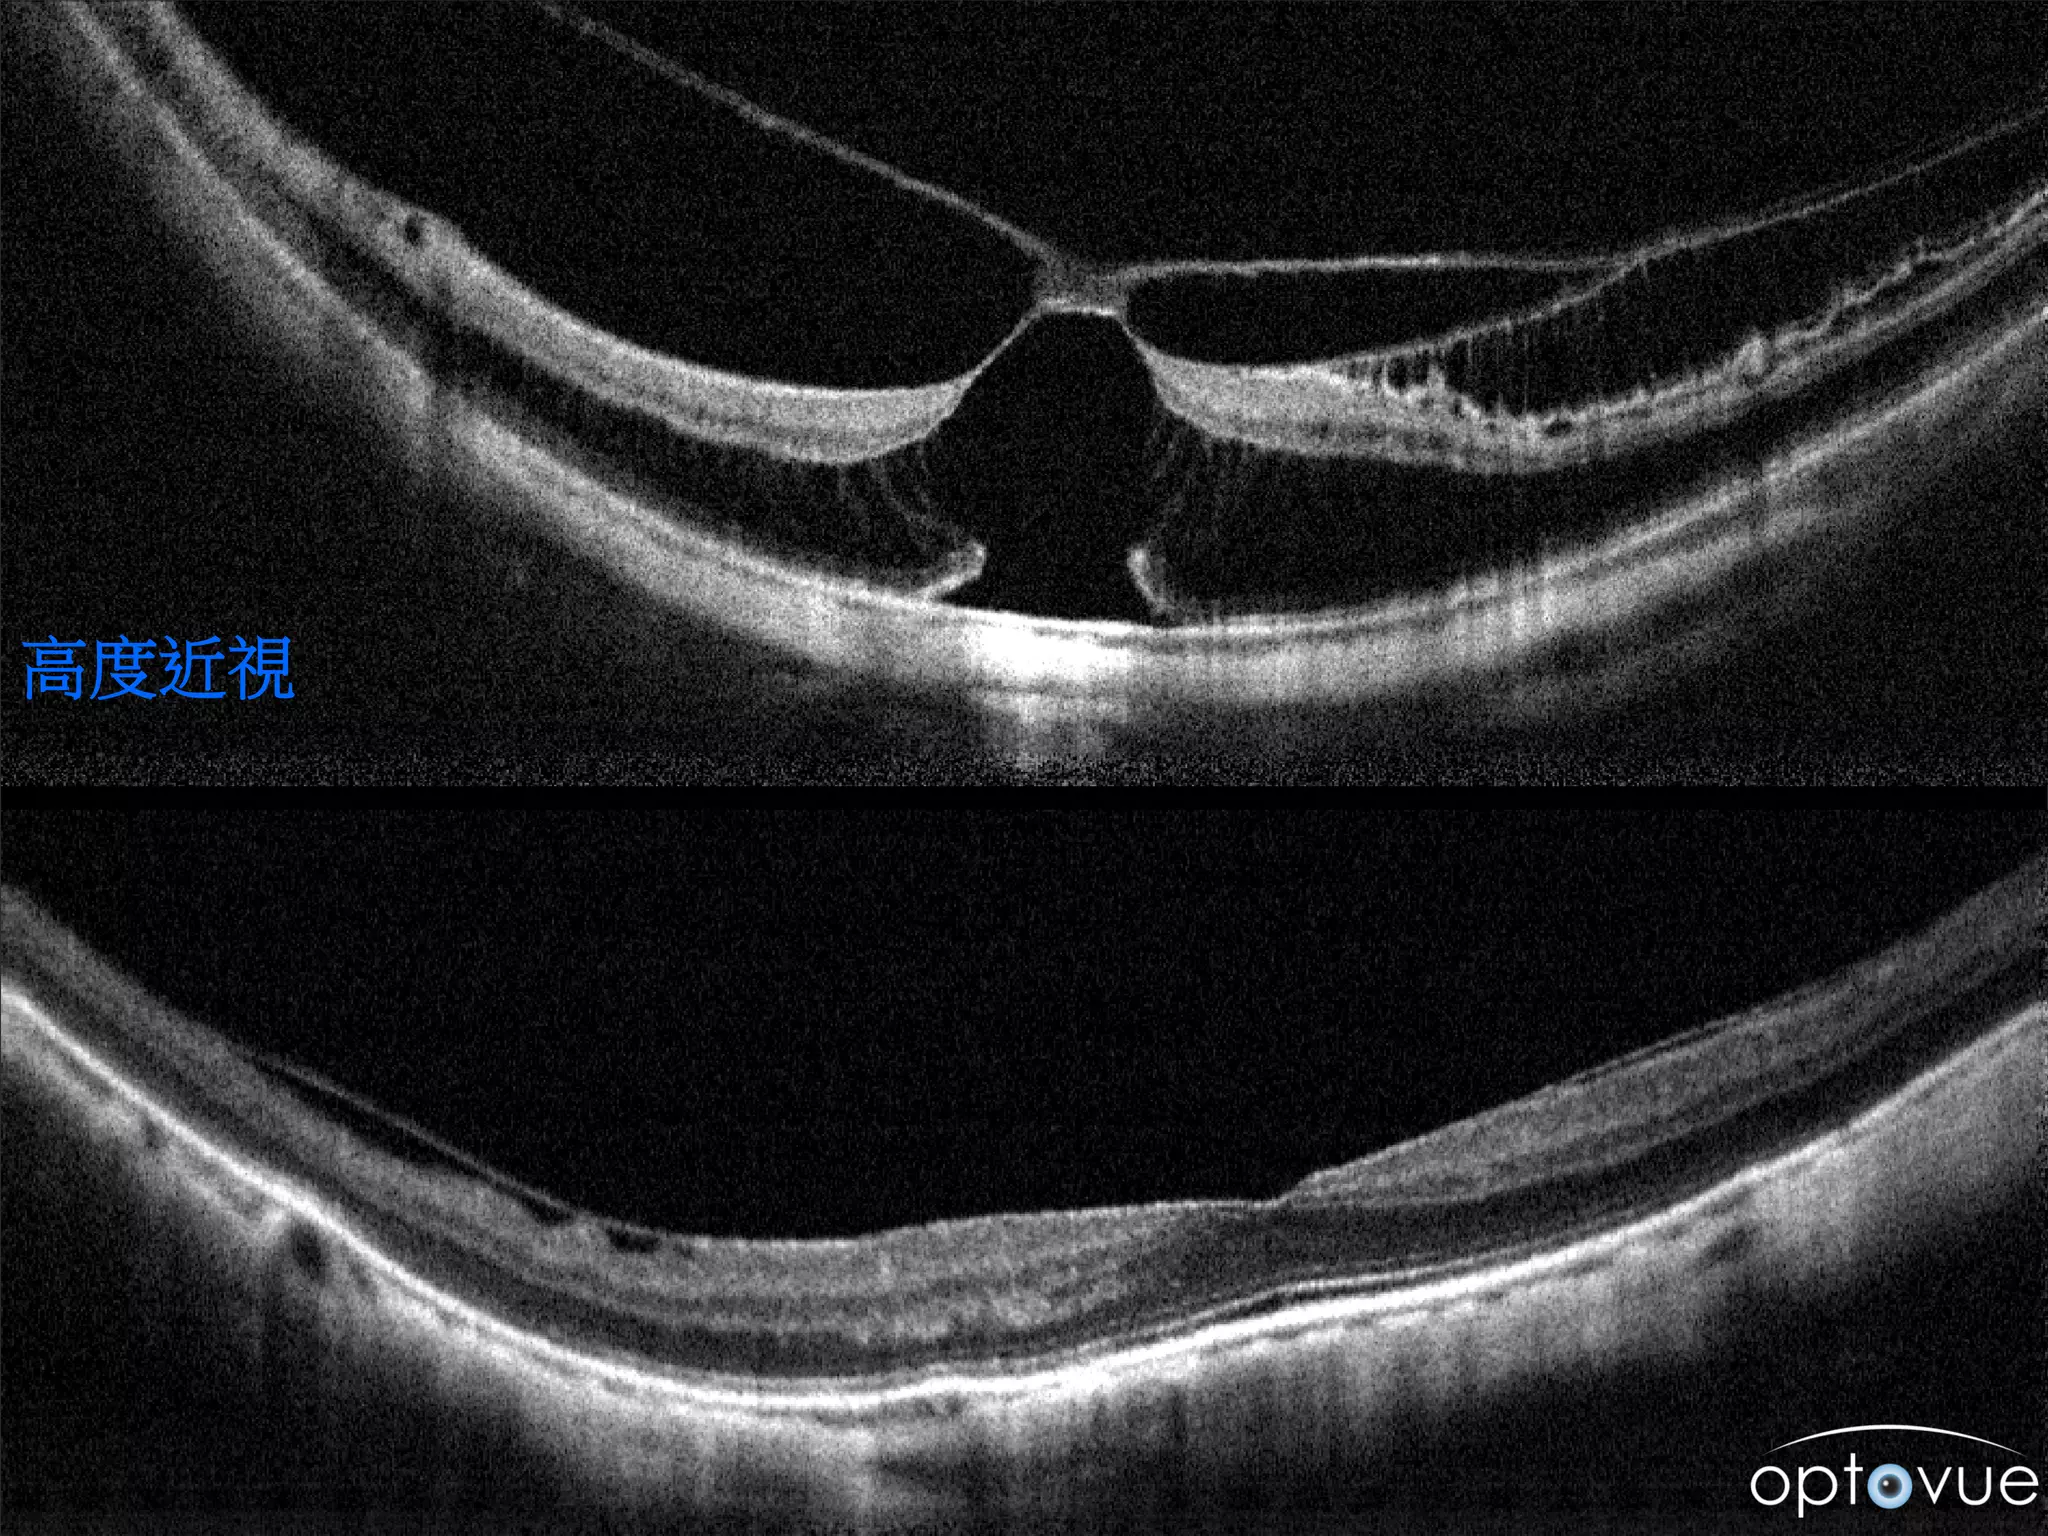

高度近視

視網膜常用掃描模式 • Cross linescan • 0.156 seconds • 2 x 1024(16 scans in each direction are then averaged) • 結構的觀察